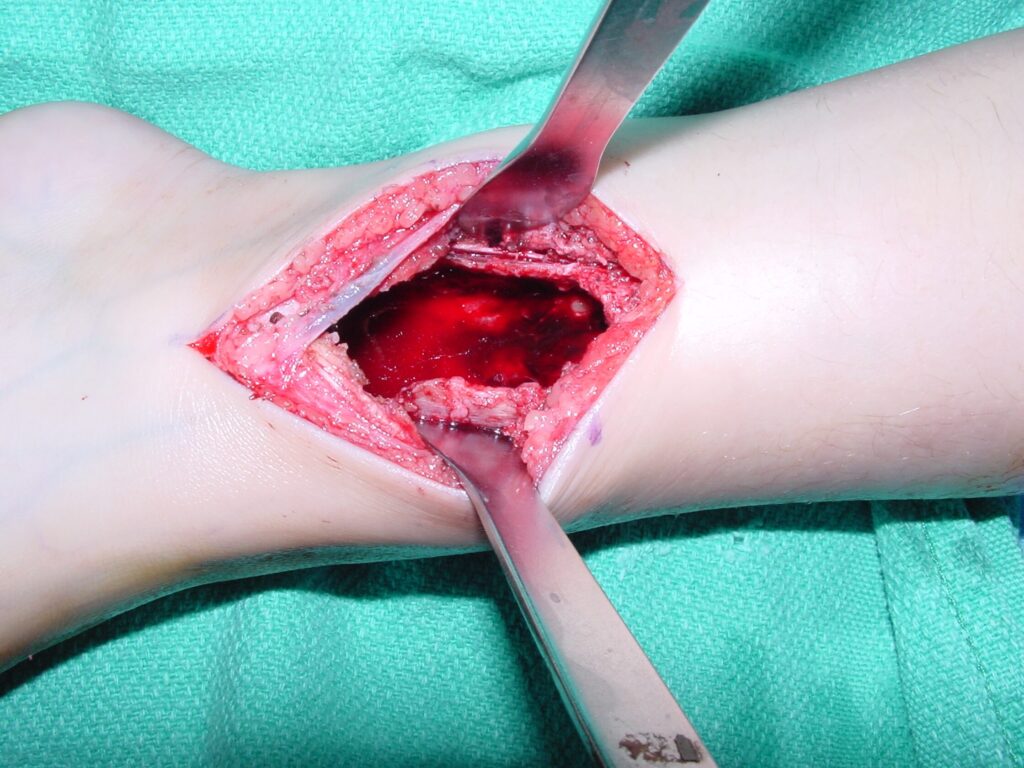

Treatment

- Intralesional curettage and bone grafting

- Adjuvant therapy is frequently used to eliminate microscopic tumor cells and decrease the risk of local recurrence

o Cryotherapy reduces the risk of local recurrence to an overall rate of 5%

Fig 4. Intraoperative photograph showing a curettage of an ABC of the distal tibia through a medial approach. The tumor is usually curetted and then the cavity is shaved down with a midas rex burr. This is called a resectional curettage and reduces the risk of local recurrence. Additional adjuvants such as liquid nitrogen may be used to treat the cavity and irradicate microscopic tumor cells. The cavity is usually filled with bone graft or bone cement. Fixation devices may be used in specific situations to prevent postoperative fracture.